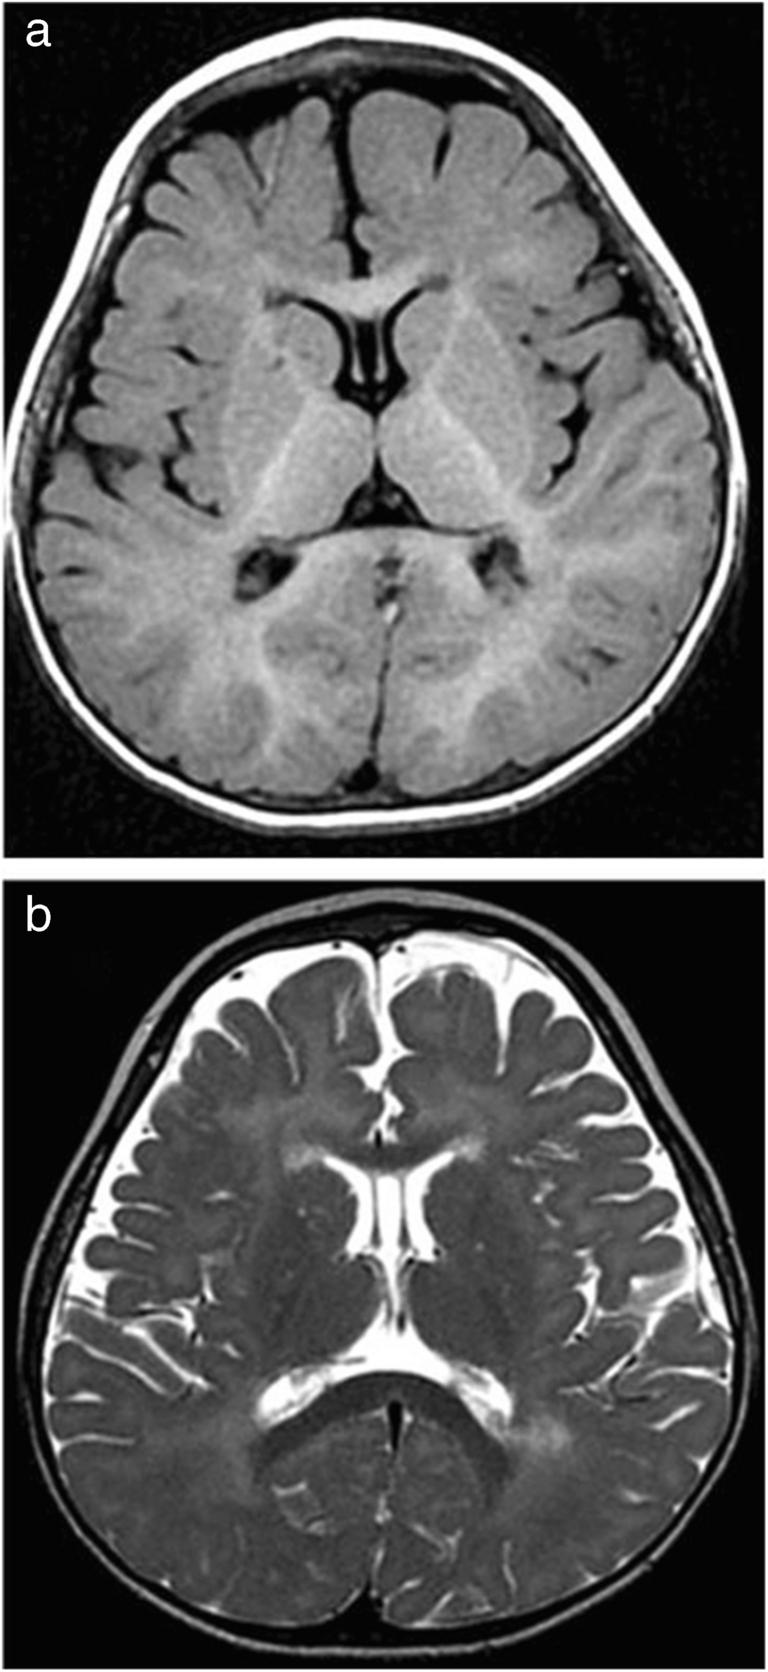

Fig. 3

Magnetic resonance angiography (3D time-of-flight) of the brain in a 4-year-old-girl with Aicardi-Goutières syndrome. a Long stenosis of the right posterior cerebral artery (arrowhead) and mild hypoplasia of the right internal carotid artery (arrow). b, c Severe stenosis of the left middle cerebral artery origin with a dilated collateral arterial network (long arrows)

The girl underwent successive brain imaging. At 15 months of age, the spinal-cord magnetic resonance imaging (MRI) findings were normal, and brain MRI revealed delayed myelination and T2 hypersignals in the periventricular white matter (Fig. 1). At 2 years and 6 months of age, brain MRI additionally revealed symmetrical clusters of hyposignals on susceptibility-weighted images, suggesting calcifications in the periventricular frontal white matter. Therefore, brain computed tomography (CT) was performed (at the age of 3 years and 2 months), and the findings confirmed the scattered calcifications in the periventricular frontal white matter and in the lenticulate nuclei (Fig. 2). These results suggested Aicardi-Goutières syndrome or pseudo-TORCH syndrome; however, TORCH infections were excluded. Trio-based whole-genome sequencing revealed a homozygous p.Arg290 Cys variant in the SAMHD1 gene (Chr20(hg38):g.36917034G>A;NM_015474.4:c.868 C>T). Each parent was heterozygous for the variant. This variant has previously been reported in a patient with interferonopathy and was considered pathogenic (class 5 according to the American College of Medical Genetics and Genomics) [3]. This finding led to the performance of another brain MRI with 3D time-of-flight (TOF) angiography at 4 years and 3 months of age, which revealed severe stenosis of the left middle cerebral artery origin, with a dilated collateral arterial network (moyamoya syndrome); long stenosis of the right posterior cerebral artery; and mild narrowing of the right internal carotid artery (Fig. 3). No ischaemic lesions were detected on diffusion-weighted, T1-weighted, or T2-weighted images. Even retrospectively, no obvious intracranial arterial stenosis was visible on conventional MRI sequences. Retrospectively, brain CT revealed mild hypoplasia of the right carotid canal at the level of the petrous bone (Fig. 2). The narrowing of the right internal carotid artery was considered a congenital anomaly (i.e., hypoplasia) rather than an acquired process (i.e., stenosis).

The identification of a homozygous variant of the SAMHD1 gene was clinically significant because this variant is frequently associated with multiple vascular anomalies, including stenoses, particularly of the distal portion of the internal carotid artery (moyamoya syndrome), aneurysms, and calcifying microangiopathy [2, 5, 6]. This finding led us to perform an additional MRI, including 3D TOF angiography, which enabled the identification of multiple intracranial arterial stenoses before the occurrence of ischaemic lesions.